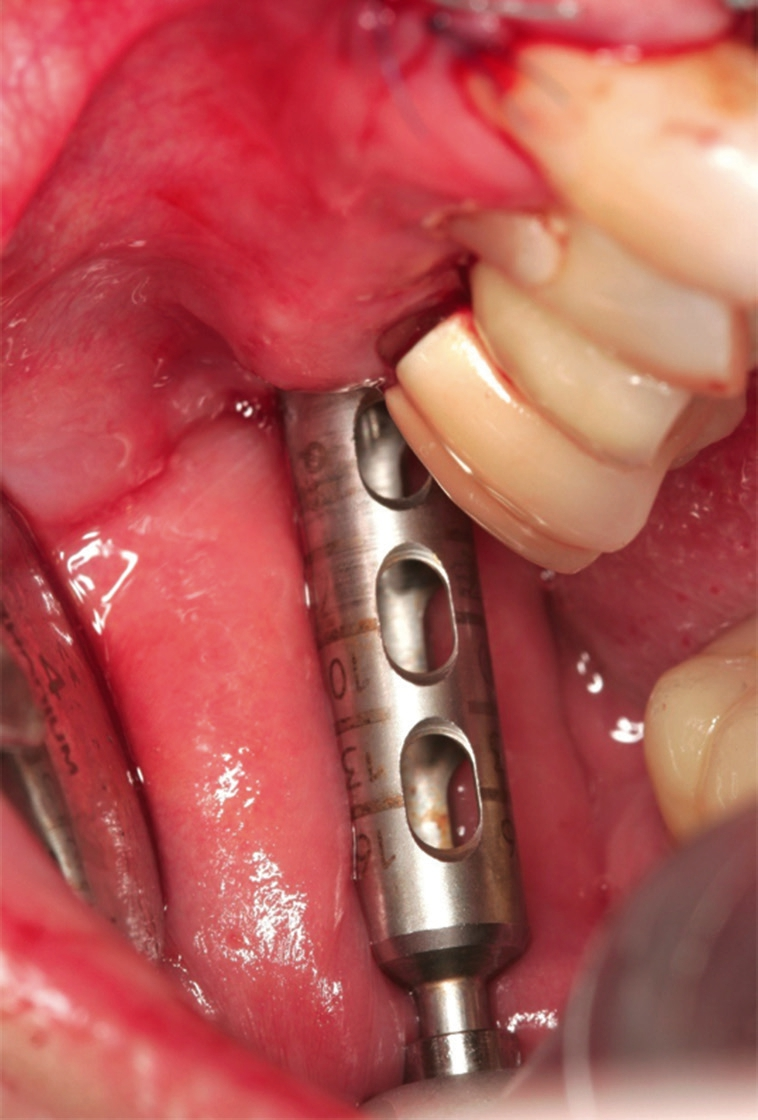

Nach Extraktion der Zähne 12, 22, 11, 21 wurde mit dem Behandlungsprotokoll für maxgraft® bonering begonnen. Nach Pilotbohrung zur Festlegung der Implantatposition wurde mit einem 6 mm Trepan die Augmentationsstelle des maxgraft® bonerings vorbereitet (Abb. 5). Danach folgte das Planieren des Ringbettes mit einem 6 mm Planator, um ein flaches Ringbett zu generieren (Abb. 6).

Anschließend wurde das Implantatbett durch den Ring vorbereitet und ein Straumann Bone Level Tapered (BLT) Implantat ø 3,3 mm gesetzt (Abb. 7 und 8). Insgesamt erfolgte die Implantation von zwei maxgraft® bonerings 6 mm und zwei Straumann BLT Implantat ø 3,3 mm 10 mm (Abb. 9). Zur Unterstützung der Weichgewebeheilung wurde platelet-rich fibrin (PRF) aus dem Blut der Patientin gewonnen (Abb. 10). Das PRF wurde sowohl in Verbindung mit dem Knochenersatzmaterial (cerabone®) (Abb. 11), als auch als Membran über der Barrieremembran (Jason® membrane) (Abb. 12) eingesetzt. Zum Erhalt der 1er Schneidezähne wurde eine Socket Preservation mit einem Knochen-Schleimhaut-Transplantat aus der tuber maxillae durchgeführt (Abb. 14 und 15). Explantation erfolgte mithilfe eines 6er Trepans rechts und links aus dem Kieferkamm (Abb. 14).